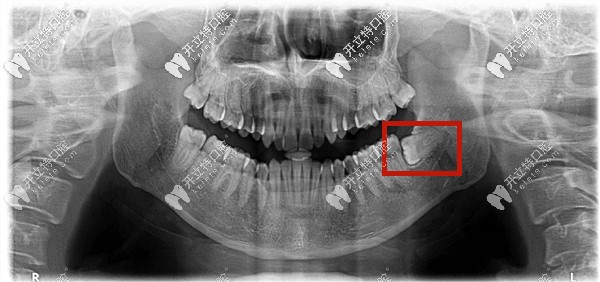

什么是低位阻生齒——就是下頜的阻生智齒的牙冠部位低于前面牙齒的牙頸部以下。

低位水平阻生齒圖片

低位阻生智齒有可能造成前面相鄰牙齒的牙周病、齲病或者是牙根的吸收;

所以如果阻生智齒已經(jīng)頂?shù)角懊娴难例X,有發(fā)炎,食物塞牙的癥狀等是需要拔牙的;

如果沒有以上癥狀,也沒有冠周炎癥發(fā)生,可以考慮保留喲!

下頜低位阻生智齒圖片

低位阻生齒——就是牙的高處部位低于第二磨牙的牙頸部,它可以是近中低位,垂直低位,遠中低位等,也有可能牙全部被包埋在牙骨內(nèi),所以又稱之為骨埋伏阻生智齒。

這種情況下的智齒一般從口中看不到,需要拍片才能確定。